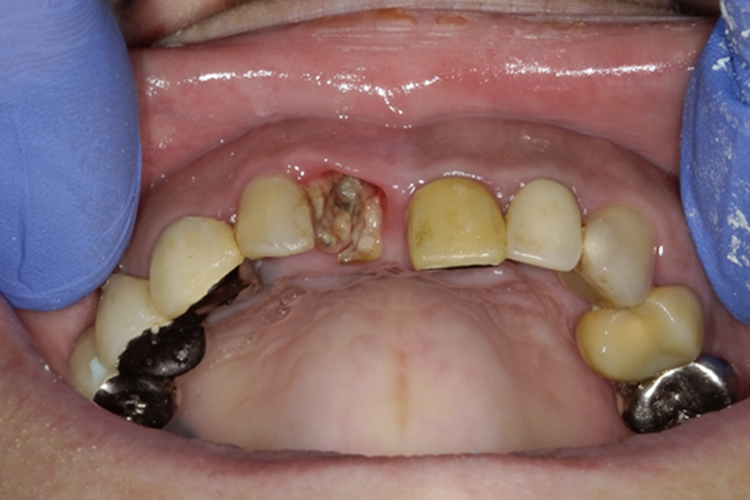

治療前

治療後